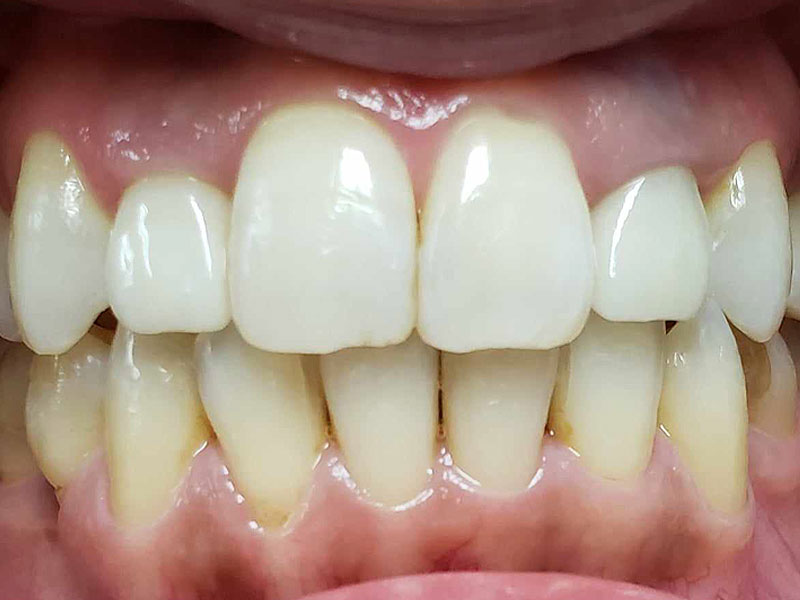

術後

約2年治療期間で包括矯正治療は完結となり、患者さんは大変満足してくれました。更にかみしめ癖も軽減し、肩こりも無くなったとのことです。口腔内写真からも舌房が確保され、舌圧痕がなくなり、かみしめ癖が軽減したことも十分にわかります。

術後10年後

着色は認められますが、ほぼ10年前の状態を維持しているように思えます。着色したCRをセラミックにという考え方もありますが、神経除去のリスクもあるため、患者さんが見た目でどおしてもと希望されないかぎり、個人的にはお勧めしません。この方も希望されませんでしたが、症状を訴えたり、確実に中が虫歯と判断しない限り、このまま経過観察していこうと考えています。